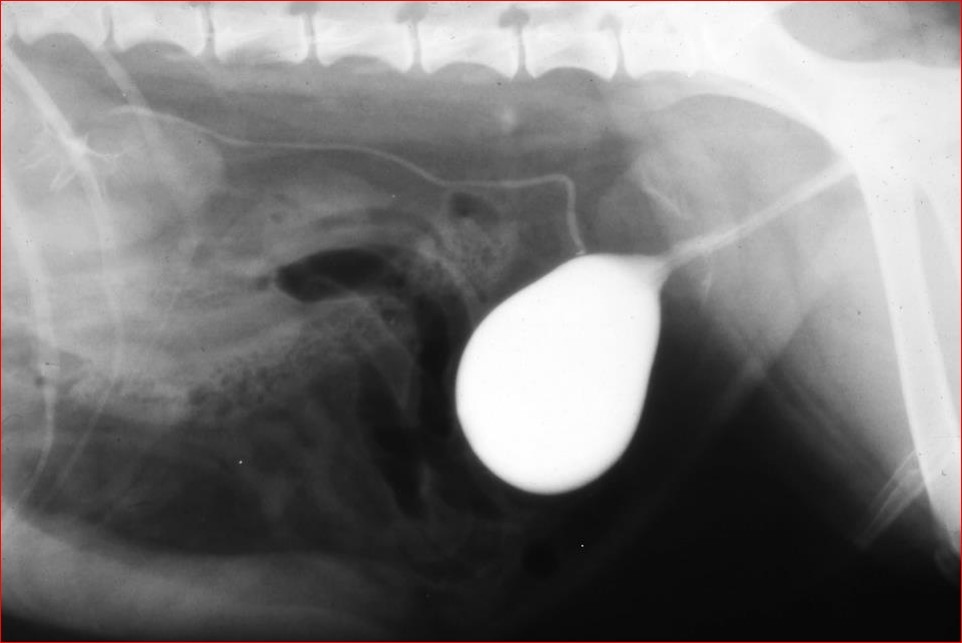

What is this?

What is the most liekly prostatic disease causing this appearance?

Pneumocysto and then contrast

Contrast has produced this appearance

What is the most likely prostatic dx causing this appearace?

Neoplasia - characteristic

NB: Cystic disease (e.g. metaplasia) – but youd never get this degree of cavity communicatin with urethra!!!